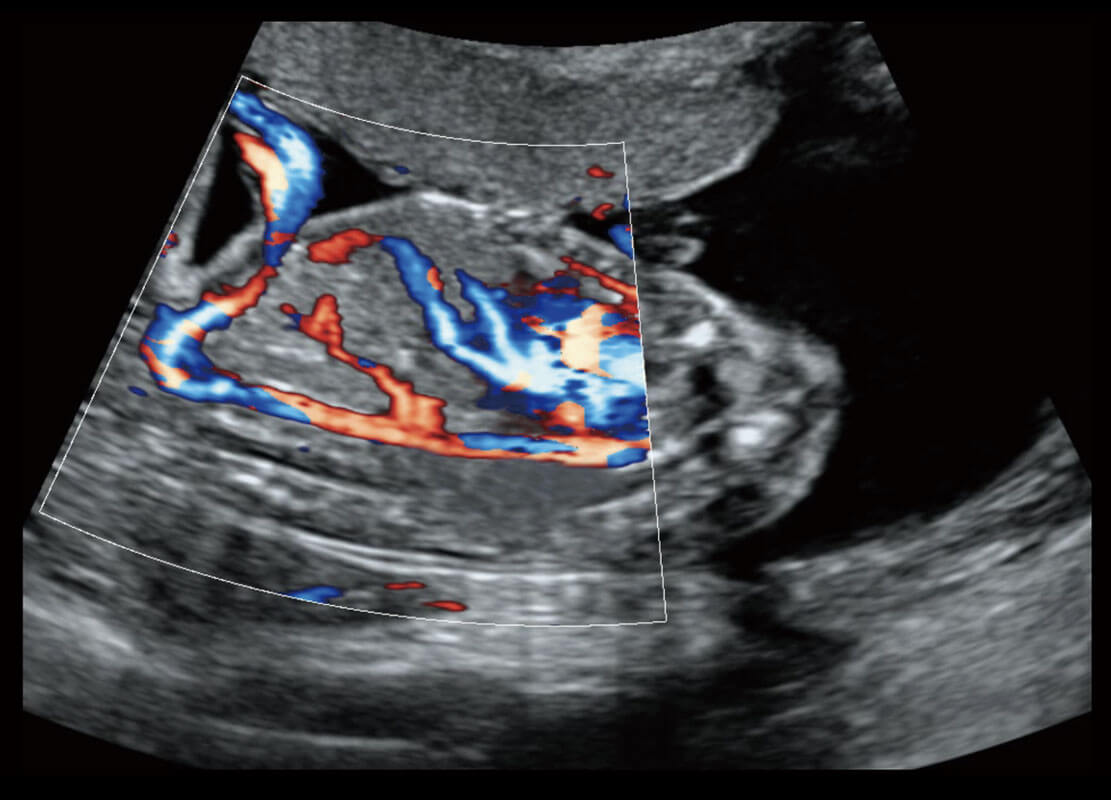

P60为盆底超声检查提供应用方案,多种腔内及腹部容积探头提供从二维、三维到四维的优异图像品质,实时快速三维容积数据获取,专业的测量工具包等人性化设计,为超声医生诊断提供有力保障。

能够简化盆底检查的操作流程,可在二维模式及三维成像模式下实现一键自动提取出标准切面、自动识别当前切面、自动测量,提升盆底检查的高效性,同时也能让青年医生快捷的获得准确的检查结果。